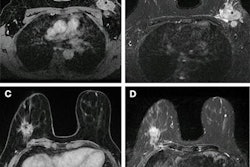

At the RUMC, different MRI protocols are used for breast imaging with MRI, depending on the purpose. Staff use a 20-minute MRI protocol for diagnostic imaging and an eight-minute abbreviated MRI (abMRI) protocol for screening. The motivation to implement abMRI is to increase cost-effectiveness.

"The idea is to be able to scan more women within the same timeframe with MRI," Koco explained. "This would therefore allow greater access to MRI screening for more women and reduce the time women have to spend inside the MRI scanner (anxiety, claustrophobia, lying still)."

With the abbreviated MRI protocol, three patients can be scanned per hour, and if diffusion-weighted imaging is omitted, it is also possible to scan four patients in one hour. Another important benefit is that the MRI scanner is almost continuously in use, she added.